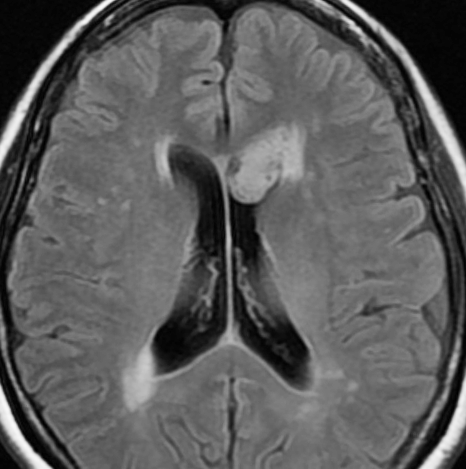

10年観察してもあまり変わらない,数が増えることがある

2012年に偶然発見され,その後,10年の経過観察されました。

2022年のものです,透明中核から出たものは少し大きくなっています。他にも数個の小さな腫瘍が脳室上壁にあるのですが,なにもしないでほっておきます。